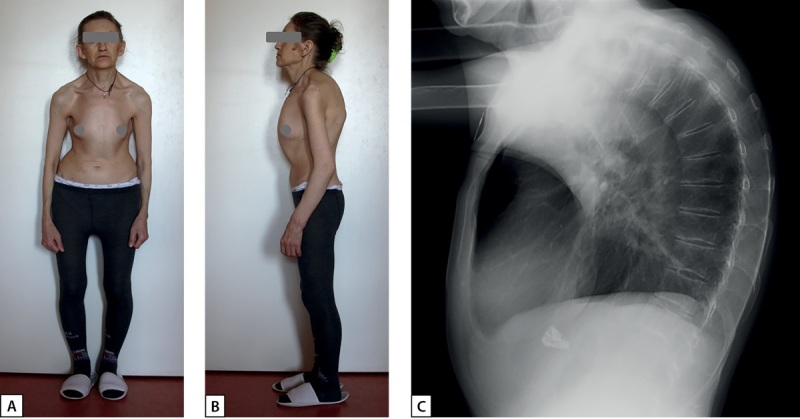

Hyperparathyroidism is a syndrome characterized by an excessive secretion of parathyroid hormone. Etiologically, hyperparathyroidism is subdivided into primary hyperparathyroidism, which develops as a result of parathyroid adenoma, carcinoma or hyperplasia, and secondary hyperparathyroidism, which happens as a compensatory response to a hypocalcemia caused by condition outside the parathyroid glands. Turner syndrome may also be accompanied by mineral metabolism disorders of various etiology. An association of hyperparathyroidism and Turner syndrome is interesting because of multifactorial impact on bone mineral density, but only few cases of such coexistence have been previously described in the literature. This article describes two patients with Turner syndrome and hyperparathyroidism of different etiology. Hyperparathyroidism, normocalcemia, vitamin D deficiency, osteoporosis, parathyroid tumors were found in both cases. In one case a number of assays was performed to confirm the patient's normocalcemic primary hyperparathyroidism, and surgery was performed to achieve remission. In the second case, treatment of vitamin D deficiency resulted in normalization of serum concentration of parathormone, after which the patient was prescribed antiresorptive therapy. The pathogenetic association between Turner syndrome and hyperparathyroidism requires further investigation. Comprehensive approach to the diagnosis and treatment of mineral metabolism disorders are essential for patients with coexistence of these two diseases.